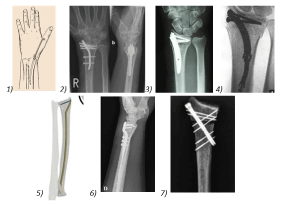

Figure 5. Different nails for the distal radius fractures 1) Rusch nail (1955), 2) “targon’’® nail, 3) “micro-nail’’®, 4) “Sonom’’®nail, 5) “Rin’’®nail, 6) “DNP’’® dorsal nail-plate, 7) Zimmer“X-Screw’’®locked screw